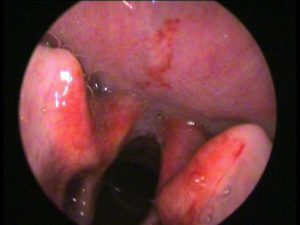

Il termometro che scende drasticamente ed ecco che i più piccoli rischiano di tossire senza sosta “con un suono somigliante a quello della foca o di un cane che abbaia“. E’ colpa della laringite “una patologia respiratoria prevalente in inverno secondaria ad infezioni virali, maggiormente virus parainfluenzali e virus respiratorio sinciziale. Colpisce il 2-3% dei bambini ed è frequente causa di accesso in pronto soccorso. Prevale tra i 6 mesi e i 3 anni di vita, con un picco nel secondo anno“. Lo rilevano gli esperti dell’ospedale pediatrico Bambino Gesù di Roma. “Dopo 2-3 giorni di incubazione, l’esordio della laringite è improvviso, raramente più graduale – sottolineano gli specialisti – La sintomatologia è causata da un rigonfiamento (edema) della mucosa del laringe e delle corde vocali con significativa riduzione dello spazio aereo”. “La tosse è tipicamente somigliante al verso della foca o di un cane che abbaia. Si associano raucedine, pianto afono, stridore, rientramenti inspiratori, irrequietezza. La febbre è di solito non alta – ricordano i pediatri – Nelle forme più gravi, per cattiva ossigenazione, compare una colorazione bluastra (cianosi) intorno alla bocca e alle estremità degli arti, con conseguente senso di forte stanchezza”.

“La laringite è la causa più frequente di stridore laringeo, che deve essere differenziato da altre patologie: reflusso gastroesofageo, laringomalacia congenita, malformazioni vascolari congenite, anelli vascolari, corpo estraneo, epiglottite, laringotracheite batterica, ascesso peritonsillare, allergie“, evidenziano i pediatri che suggeriscono di “tranquillizzare il bambino e prediligere la posizione seduta per ottimizzare la ventilazione. Eseguire una visita medica in caso di primo episodio o solo parziale risposta alla terapia o se si associa difficoltà respiratoria“.